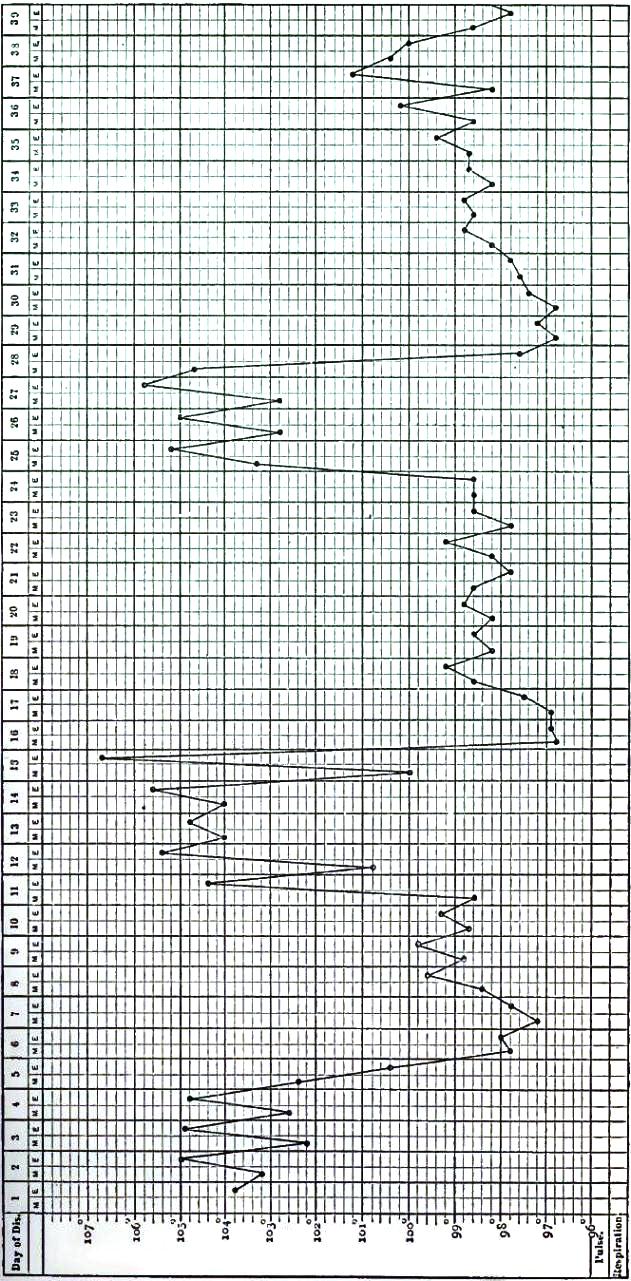

| 12. | CHART OF TYPICAL RANGE OF TEMPERATURE IN TYPHOID FEVER, AFTER WUNDERLICH |

| 13. | CHART SHOWING RECRUDESCENCE OF FEVER FROM INDISCRETION OF DIET |

| 14. | CHART SHOWING FALL OF TEMPERATURE FROM INTESTINAL HEMORRHAGE IN TYPHOID FEVER |

| 15. | PULSE-TRACING IN RELAPSES OF TYPHOID FEVER |

| 16. | CHART OF TEMPERATURE IN TYPHOID FEVER WITH RELAPSE.—ORIGINAL ATTACK |

| 17. | CHART OF TEMPERATURE IN TYPHOID FEVER WITH RELAPSE.—RELAPSE |